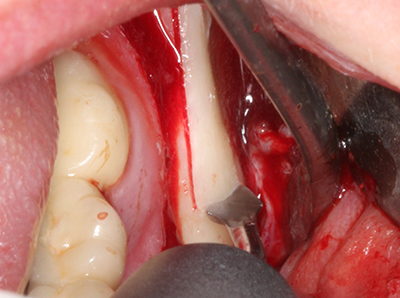

Piezo surgery has additional advantages when harvesting bone blocks. In addition to the high precision with osteotomy described above, the use of the thin saw tips specifically minimizes loss of material. Greater loss of material during harvesting can be expected with the thicker instrument tips, particularly when using Lindemann drills (Lakshmiganthan, Gokulanathan et al. 2012). The basal separation, which is necessary particularly for retromolar block transplants, is simplified by specially designed rectangular saws, with the result that piezo surgery is viewed as a precise, simple and safe procedure for harvesting retromolar bone blocks (Happe 2007) (Fig. 1-12).

When surgical procedures are performed on bone in the immediate vicinity of sensitive structures such as blood vessels or nerves, rotary instruments pose a significant risk of iatrogenic injury. Piezoelectric devices can be helpful for preparation of bone covers and removal of hard tissue close to nerves, particularly for exposure of nerves after iatrogenic injury but also during nerve lateralization for resective and reconstructive procedures or implant placement (Fig. 17-20). Light contact between the piezotip and the nerve does not generally result in damage but proceeding incautiously with saw-like motions or attachments where a residual bone substrate remains may cause temporary or even permanent nerve damage. However, the risk of damage is considered to be substantially lower than when using saws or milling instruments (Pereira, Gealh et al. 2014).